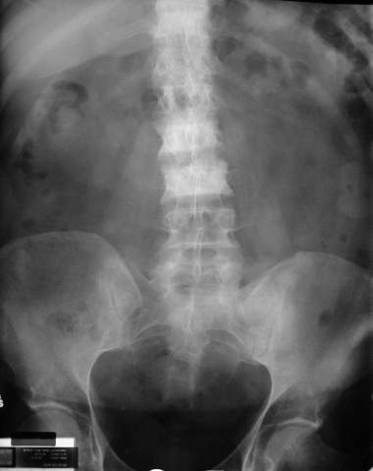

LAPORAN PENDAHULUAN PADA PASIEN DENGAN TUMOR ABDOMEN A ...

Lunak. 4) Kadang tampak hipervaskulari disekitar tumor. 5) Biasa terjadi pengerutan dam mengalami retraksi. 6) Edema disekitar tumor disebabkan infiltrasi kepembuluh limfe. 7) Nyeri jaringan, aspirasi dan eksisi tumor yang kecil. 7) ... Access Doc